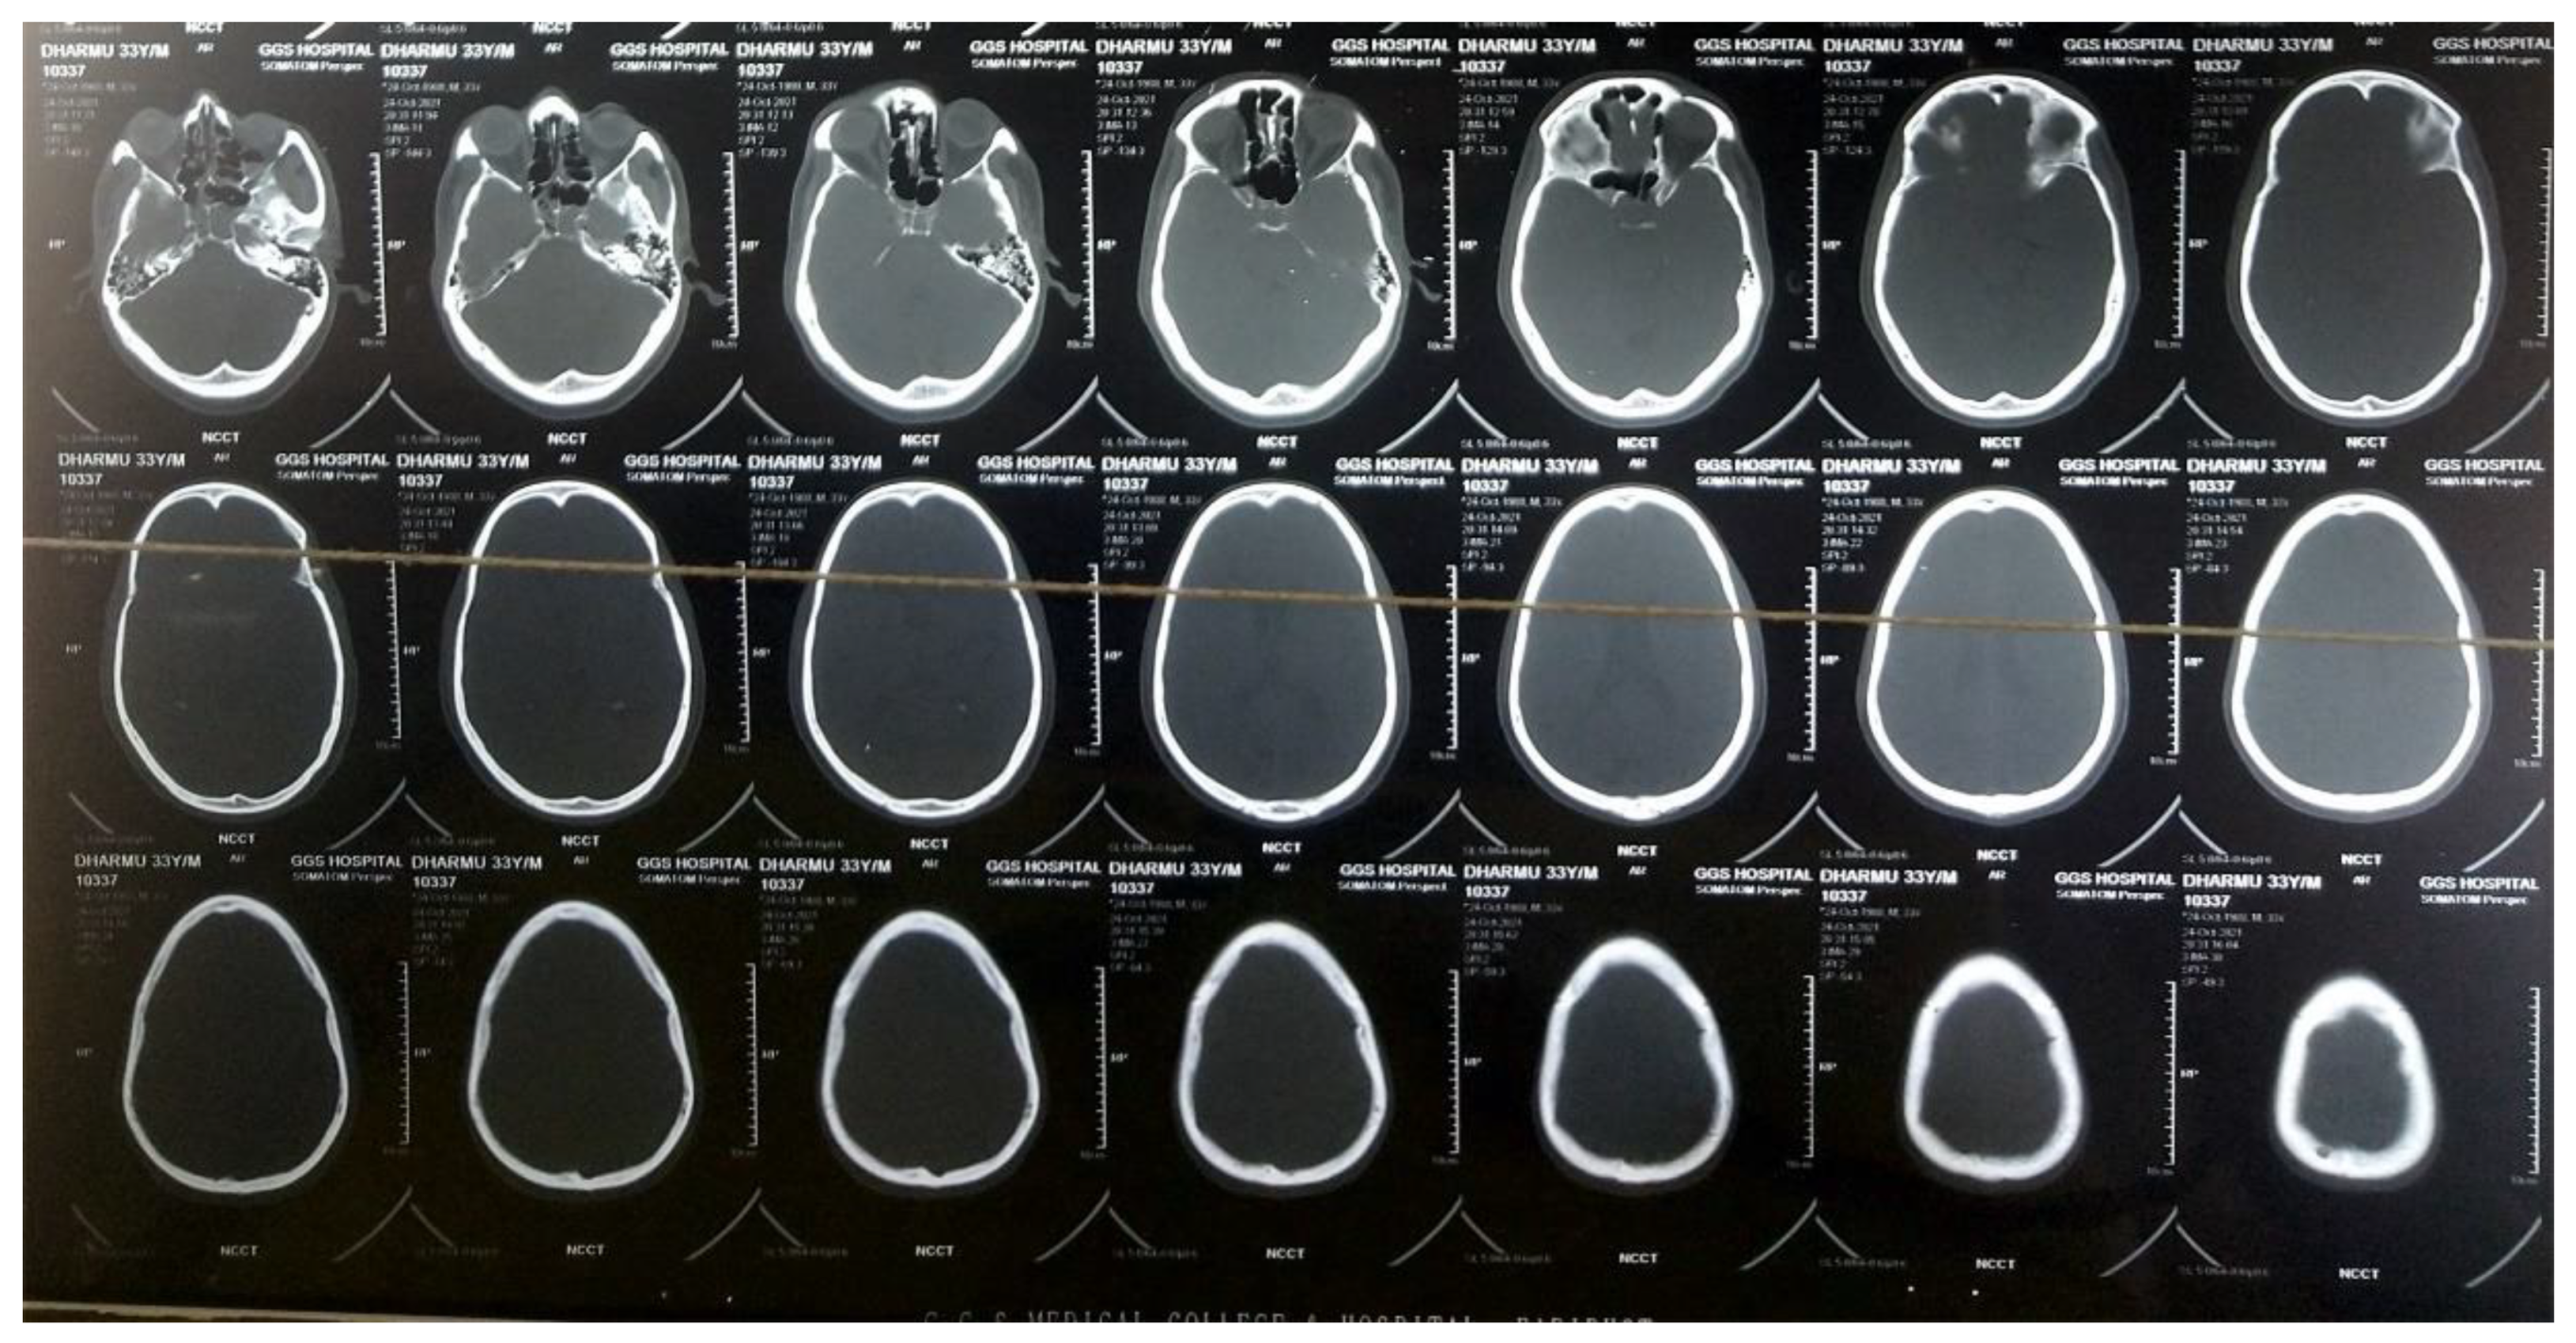

2. Case Presentation

3. Investigations